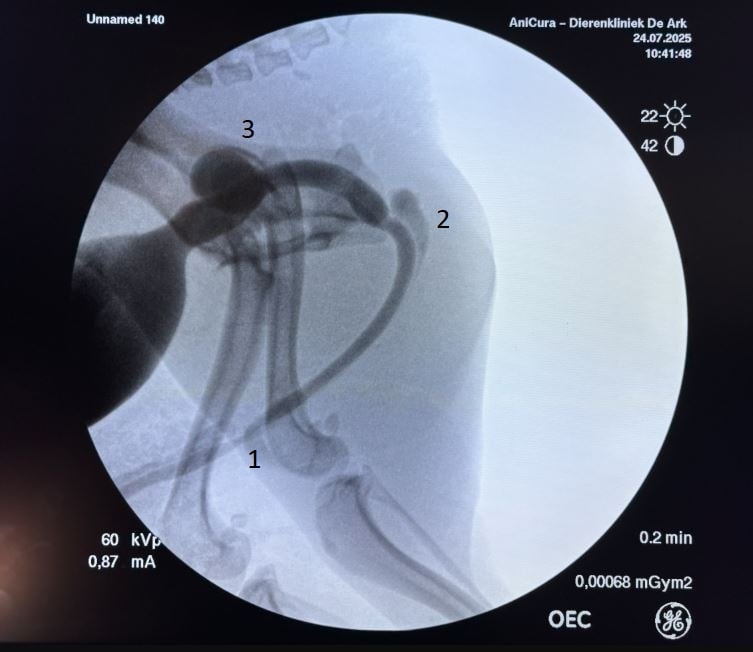

Met de camera kon een strictuur worden vastgesteld net achter het penisbot, maar ook met de camera kon de strictuur niet gepasseerd worden. De hond werd opnieuw gesondeerd tot aan de strictuur, waarna er contrastvloeistof werd ingebracht en met de fluoroscoop beelden werden gemaakt. Op deze beelden is de strictuur van de urethra (1) zichtbaar. Ook werd een divertikel van de urethra thv de bekkenomslag (2) en de prostaatcyste (3) duidelijk zichtbaar door het gebruik van het contrast. De prostaatcyste en het divertikel zijn vermoedelijk ontstaan door een chronische overdruk gecreëerd door de urethrale strictuur.